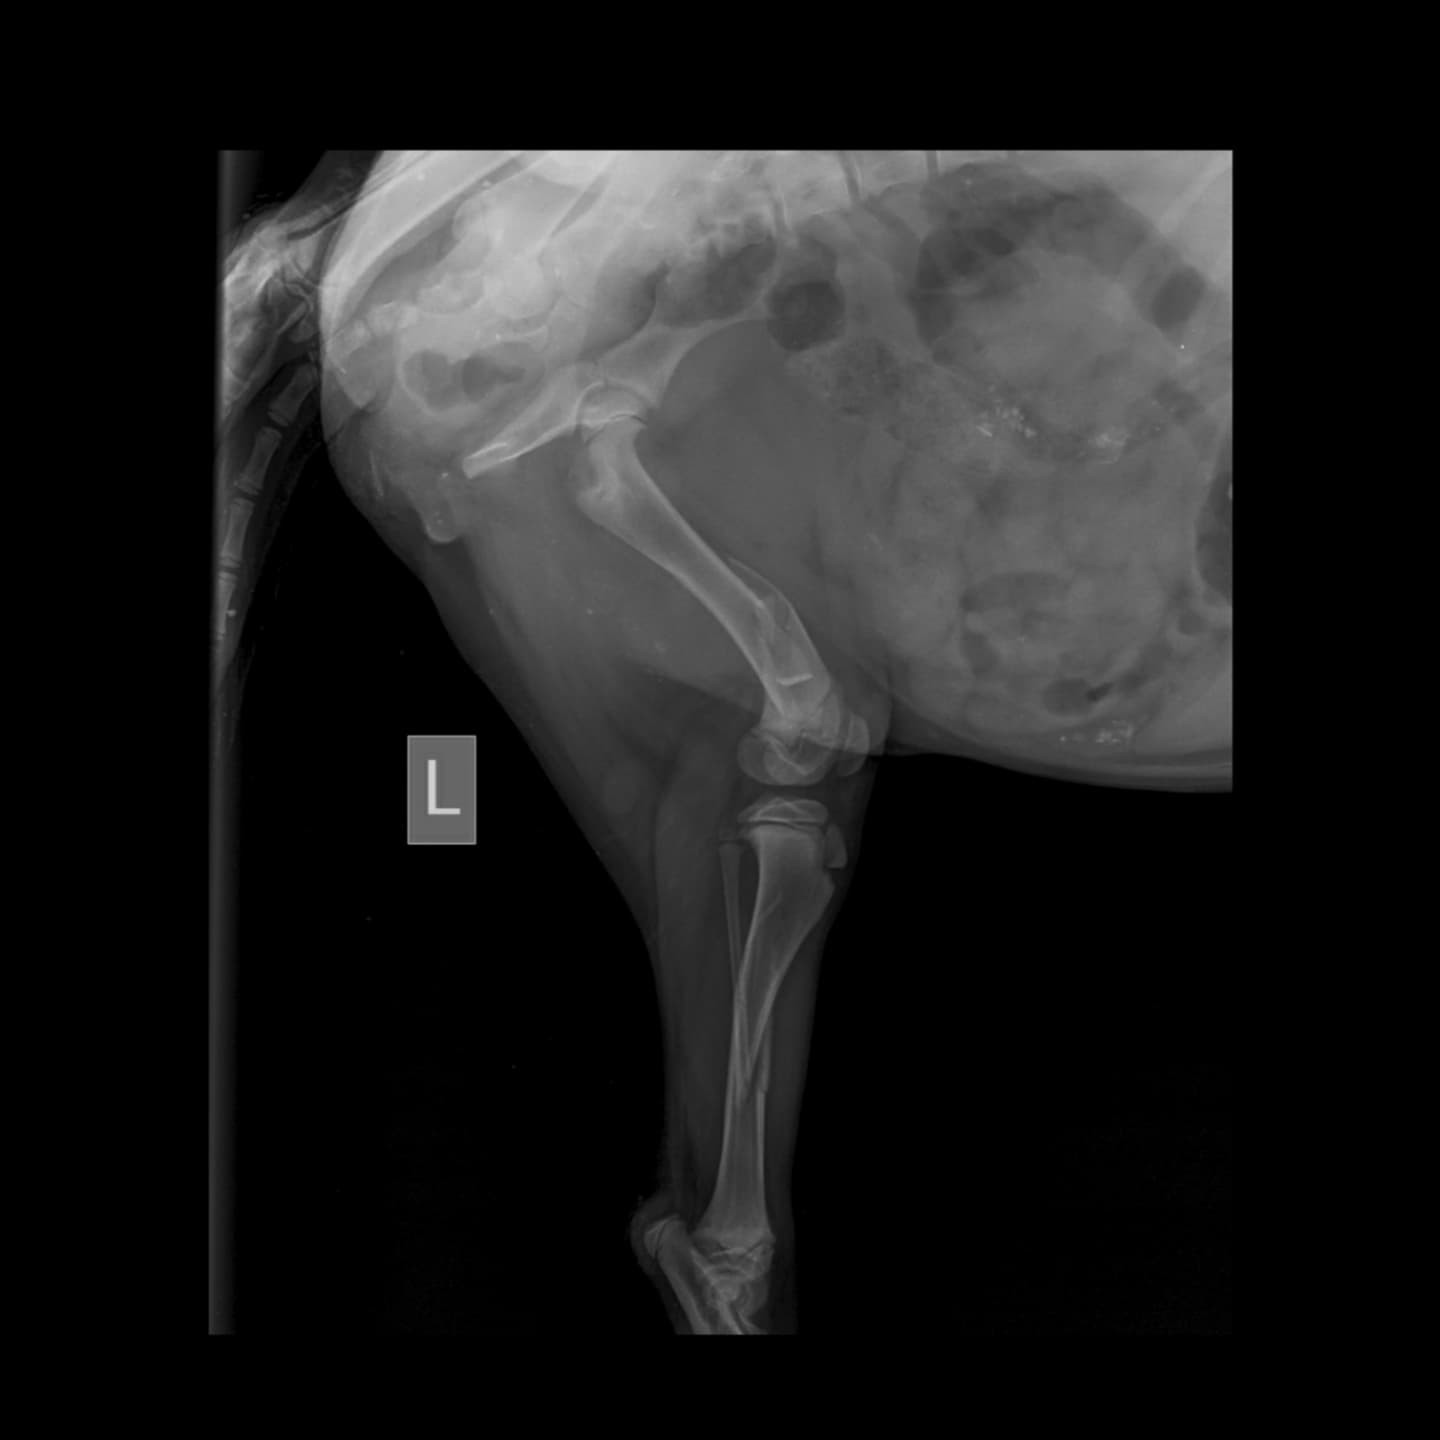

This little girl, MAPLE, all of 4-5 months was in a hit and run this evening. Second case within an hour of each other. The other one was killed on the spot. This one has multiple fractures on her leg. It’s a long road to recovery. We don’t know how and what is going to happen . Initial check up has been done and we have been informed that she will need surgery. Surgery is going to cost 25-30k and then shelter/foster care .

The last pic is today’s initial bill.